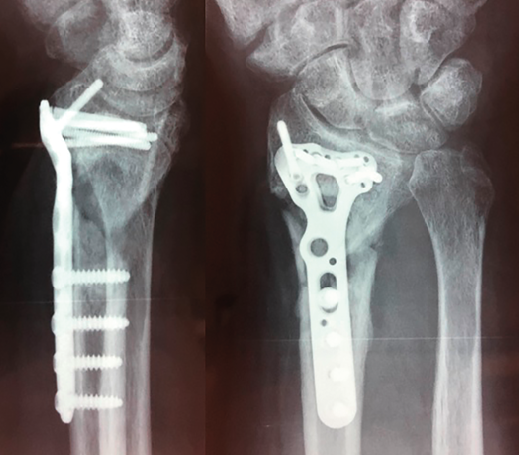

Figura 1. Radiografía simple y tomografía computarizada de fractura.

Se realiza radiografía simple y tomografía axial computarizada (TAC) (Figura 1). Se llevó a cabo la osteosíntesis con una placa volar Acu-Loc 2® distal ancha larga de Acumed y aporte de hueso de banco liofilizado en el foco metafisario. Se consiguió una reducción correcta (Figura 2). La herida evolucionó sin incidencias y se mantuvo al paciente 3 semanas inmovilizado con férula en U bloqueando la pronosupinación (sugar tongue). Posteriormente, inició una rehabilitación progresiva, con uso de ortesis rígida de descarga y controles clínicos y radiológicos cada 4-5 semanas.